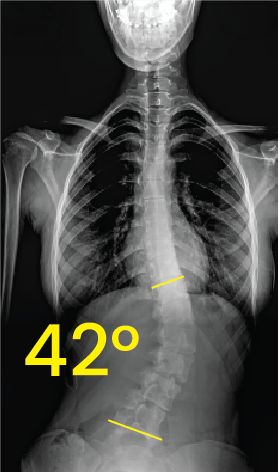

Göğüs ve belde 42 derece eğriliği gösteren omurga röntgeni görüntüsü.Dorsal X-ray image showing spinal curvature with a 28-degree angle measurement indicating scoliosis.